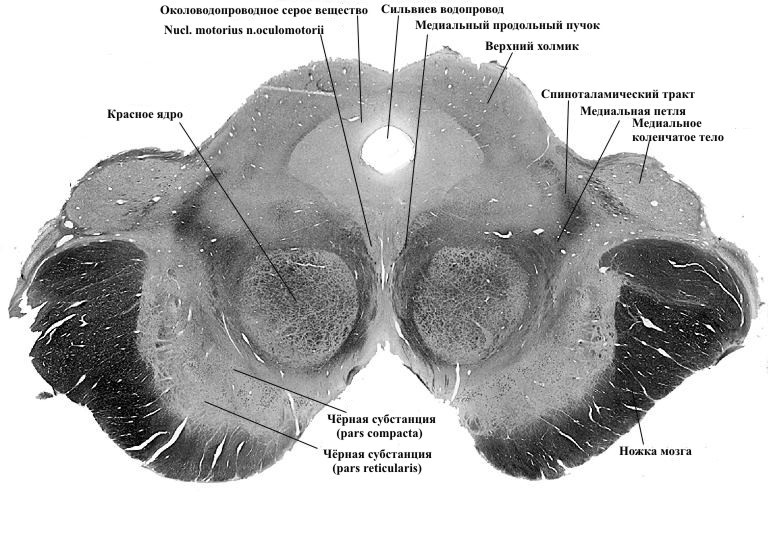

Внутреннее строение. На поперечном разрезе среднего мозга в ножке мозга отчётливо выделяется своим тёмным цветом (за счёт содержащегося в нейронах меланина) чёрное вещество, substantia nigra. Оно простирается в ножке мозга от моста до промежуточного мозга. Условно чёрное вещество делит ножку мозга на два отдела: дорсальный – покрышка среднего мозга, tegmentum mesencephali, и вентральный отдел – основание ножи мозга, basis pedunculi cerebri.

Кроме того, на поперечном срезе среднего мозга видна полость, которая представляет собой на протяжении узкий канал длиной около 1,5 см. Этот канал называется водопроводом среднего мозга, aqueductus mesencephali, соединяет полость III желудочка с полостью IV желудочка и содержит спинномозговую жидкость. По своему происхождению водопровод мозга является производным полости среднего мозгового пузыря.

Покрышка среднего мозга простирается от чёрного вещества до уровня водопровода мозга. В покрышке среднего мозга залегают ядра среднего мозга и проходят восходящие проводящие пути. Самым заметным ядром является красное ядро, nucleus ruber, в пределах которого выделяют краниально расположенную мелкоклеточную часть и каудально расположенную крупноклеточную часть. Красное ядро имеет удлинённую форму и простирается от уровня нижних холмиков до таламуса. Своё название это ядро получило в связи с наличием тонкой обильной васкуляризации составляющих его структур. От красных ядер начинается красноядерно-спинномозговой путь и в них заканчивается большая часть волокон верхних мозжечковых ножек.

В покрышке мозга, латерально и кверху от красного ядра, виден пучок волокон, входящих в состав медиальной петли, lemniscus medialis. Нервные волокна, входящие в состав медиальной петли, формируются за счёт так называемых внутренних дугообразных волокон, fibrae arcuatae internae. Последние являются отростками клеток ядер пучков Голля и Бурдаха (пути проприоцептивной чувствительности) и направляются из продолговатого мозга к ядрам таламуса вместе с волокнами общей чувствительности (температурной, болевой), формирующими спиноталамический путь, tractus spinothalamicus.

Кверху и кнутри от медиальной петли располагается ретикулярная формация, formatio reticularis.

Вокруг водопровода среднего мозга расположено центральное серое вещество, substantia grisea centralis, в котором в области дна водопровода находятся ядра двух пар ЧМН. На уровне верхних холмиков, вблизи средней линии, находится парное ядро глазодвигательного нерва, nucleus n. oculomotorii. Кнутри от него локализуется парасимпатическое добавочное ядро глазодвигательного нерва, nucleus oculomotorius accessorius (ядро Якубовича-Эдингера-Вестфаля). Волокна, отходящие от добавочного ядра, иннервируют мышцу, суживающую зрачок и ресничную мышцу. Здесь же находится одно из ядер ретикулярной формации – промежуточное ядро, nucleus interstitialis (ядро Кахаля). Отростки клеток этого ядра участвуют в образовании переднего ретикулоспинального пути и заднего продольного пучка.

На уровне нижних холмиков в вентральных отделах центрального серого вещества залегает парное ядро IV пары ЧМН – ядро блокового нерва, nucleus n. trochlearis.

В латеральных отделах центрального серого вещества на протяжении всего среднего мозга располагается ядро среднемозгового пути тройничного нерва, nucleus mesencephalicus n. trigemini (V пара ЧМН). Отростки клеток этого ядра образуют в покрышке среднего мозга волокна так называемой тройничной петли, lemniscus trigeminalis, которая направляется к ядрам таламуса.

Рис. 9. Поперечный срез среднего мозга. Видны ядра, включая среднюю субстанцию (рисунок из интернета)